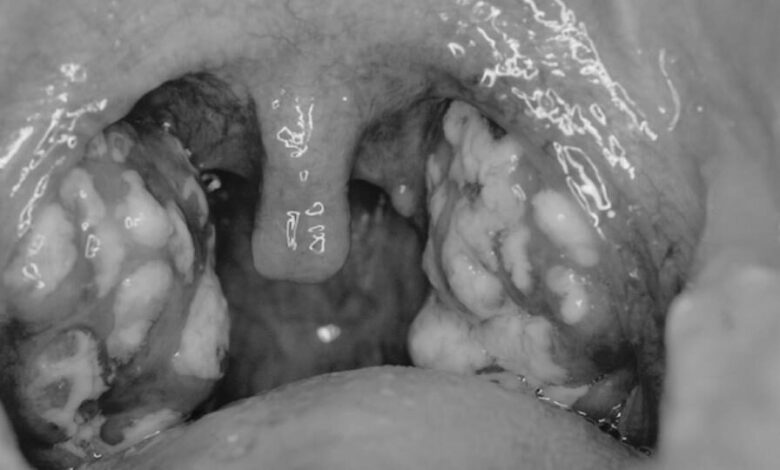

Santé : les coups de froid et poussières à l’origine de l’angine